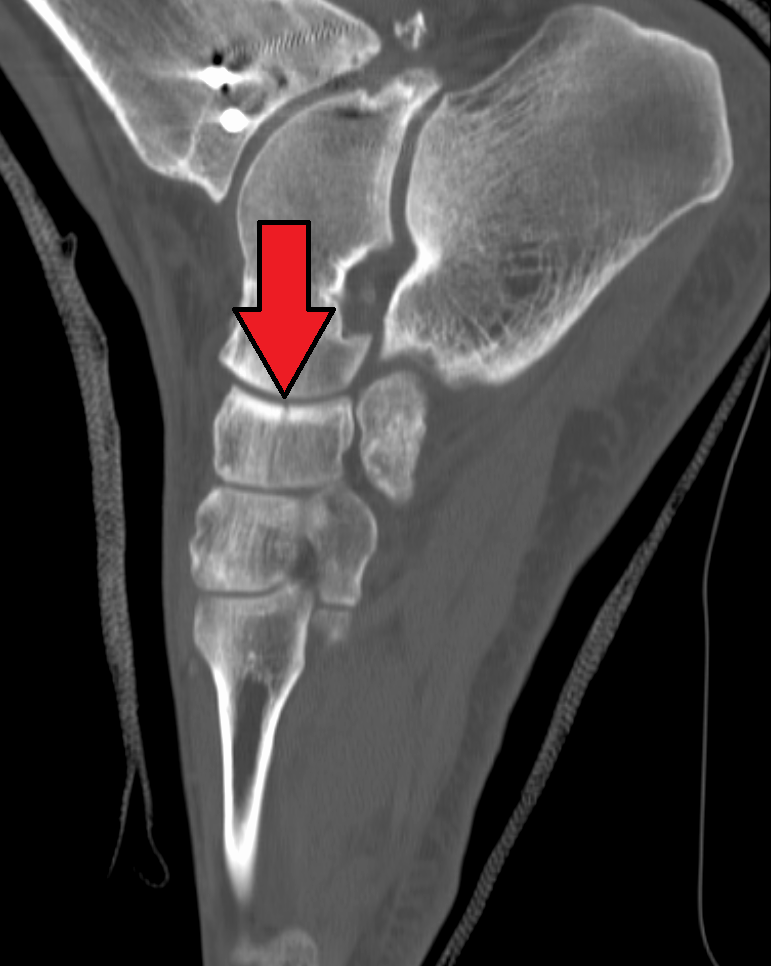

뒤정강근은 발배뼈에 부착되는 유일한 근육이다. 근육의 주요 부분은 발배뼈의 거친면에 삽입된다.[3] 덧발배뼈는 일반 인구의 2~14%에서 나타날 수 있다.[4][5][6] 사람의 발배뼈는 흔히 골절되는 뼈는 아니지만, 운동선수에게 흔히 발생하는 피로 골절[7]과 고에너지 외상, 두 가지 이유로 골절될 수 있다.

사람의 발배뼈는 흔히 골절되는 뼈는 아니지만, 두 가지 이유로 골절될 수 있다. 첫 번째는 운동선수에게 흔히 발생하는 피로 골절[7]이며, 다른 하나는 고에너지 외상이다.발배뼈는 발의 핵심 뼈로, 발목 부분의 일부이며, 목말뼈, 첫 번째, 두 번째, 세 번째 설상뼈, 입방뼈, 발꿈치뼈와 연결된다. 발의 생체역학에서 중요한 역할을 하며, 안쪽번짐, 가쪽번짐 및 움직임을 돕는다. 또한 발 중간 부분과 앞발 부분을 연결하는 구조적 연결 고리이며, 발의 세로 아치와 가로 아치의 일부를 형성한다.